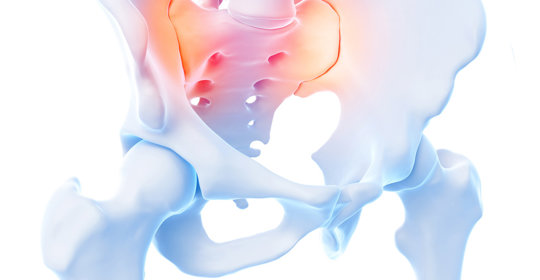

本文介紹了左下腹痛這一症狀在不同病因下的處理方式,並強調了在特定時期如孕期時的特殊考慮。面對左下腹痛,應警惕多種潛在疾病,及時尋求專業醫療幫助以確定確切原因並接受適當治療。